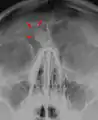

يمثل الورم العظمي أكثر أورام الأنف والجيوب المجاورة للأنف من حيث كونها حميدة. سبب الإصابة بالورم العظمي غير مؤكد، لكن النظريات المقبولة بشكلٍ عام تقترح أسباباً جنينية أو رضحية، أو معدية. كما قد يترافق الورم العظمي مع متلازمة غاردنر. قد تتسبب الأورام العظمية القحفية الأكبر حجماً بحدوث ألم في الوجه وصداع وعدوى بسبب انسداد القنوات الجبهية الأنفية. غالباً ما يظهر الورم العظمي القحفي الوجهي من خلال علامات وأعراض في العينين كجحوظ العين.[2]